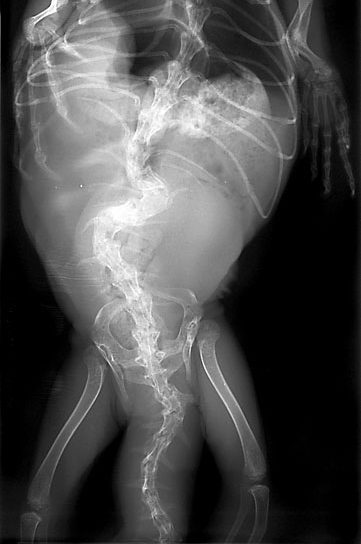

イグアナは成長が早く、2~3年で全長2m近くになります。その発育には十分なカルシウムとビタミンDが必要になります。カルシウムが少ないエサ、紫外線の不足により、成長不良、骨の菲薄や変形、骨折するような代謝性骨疾患(MBD:Metabolic bone disease)が起こります。骨

軟化症やくる病とも呼ばれることもあります。低カルシウム血症を起こして振戦がみられることもあります。